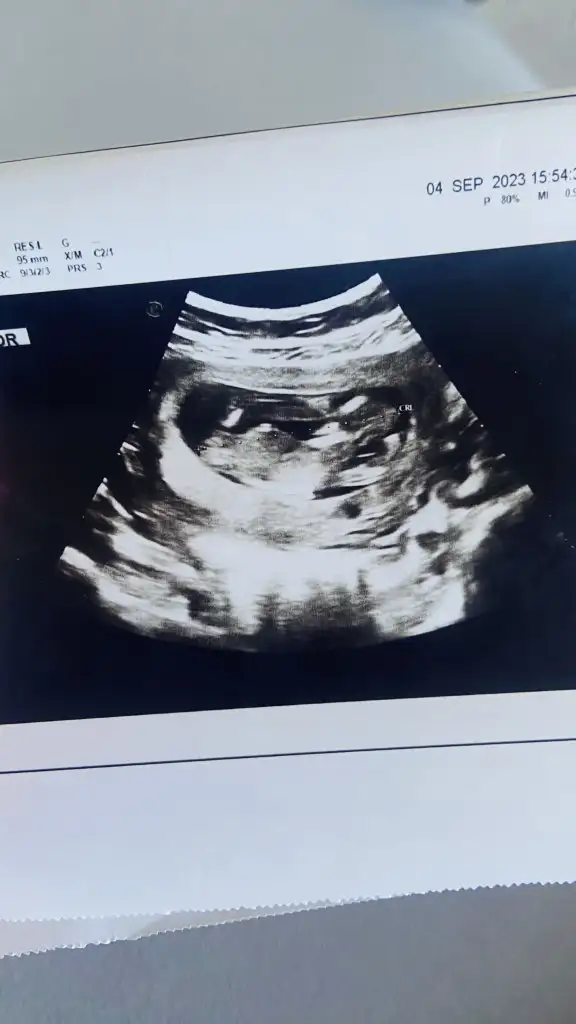

Banada tahminde bulunur musunuz lutfen 12+4 karından ultrasyon

16939936298637089910527887211289.webp

16939936891865931306224271229345.webp